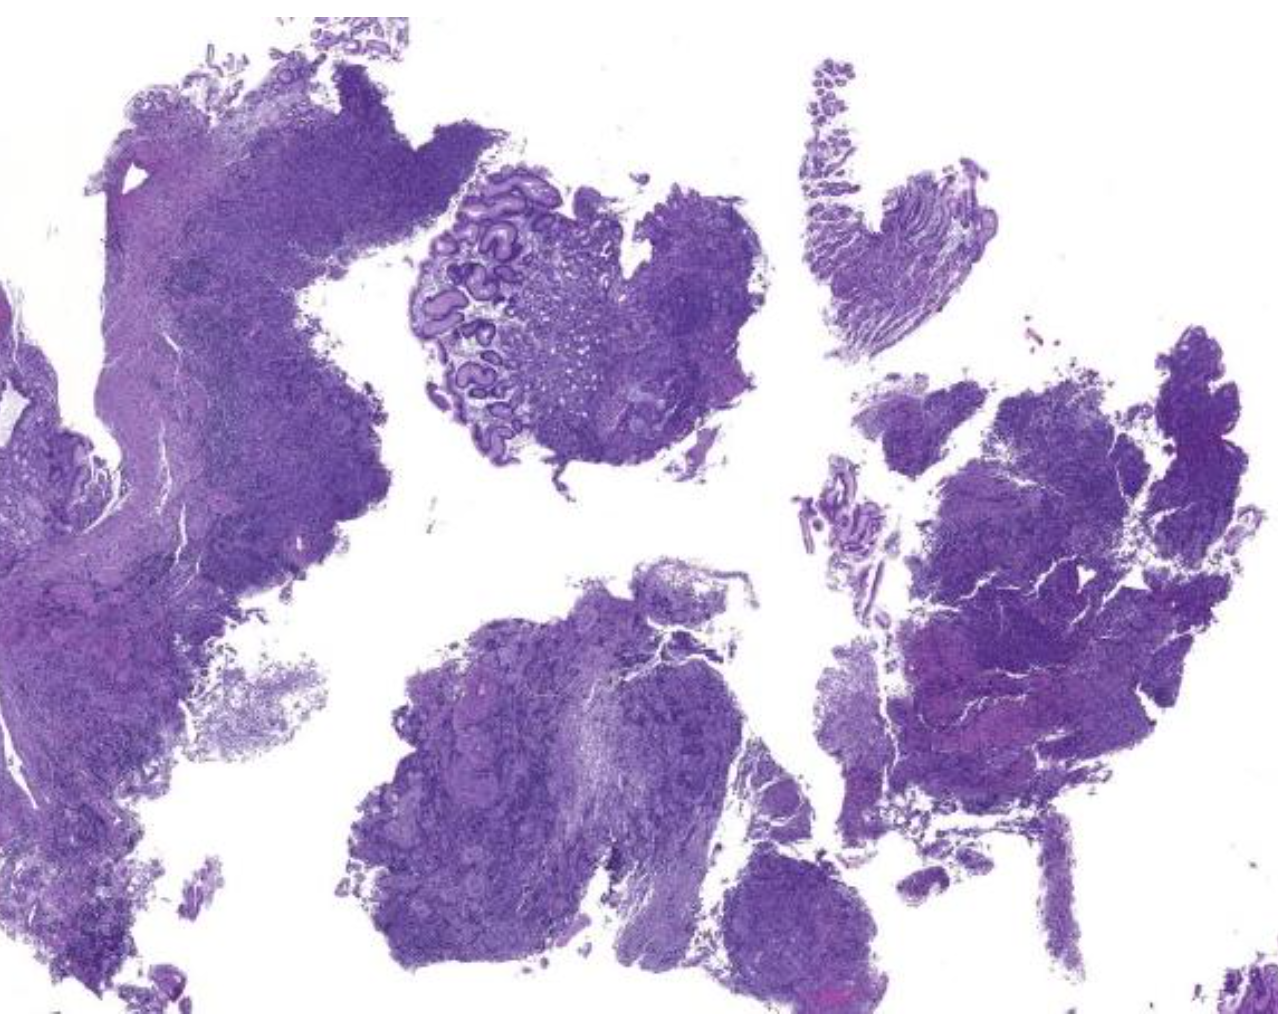

Diagnose?

Adenokarzinom des gastroösophagealen Übergangs = Barettkarzinom

Viel häufiger als Plattenepithel-CA, wird immer irregulärer je höhergradig und tieferreichender der Tumor ist, Dysplasie ist Vorstufe und Notwendigkeit zur Therapie